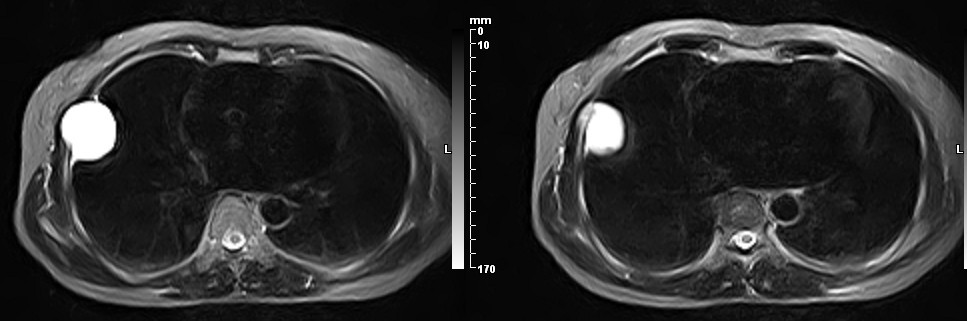

女,49岁。三年前因胸部不适在外院行CT检查诊断报告:右胸壁占位病变,考虑胸膜间皮瘤可能性大。现病人到我院检查了解情况。算是较典型的病变吧?大家看看MR比CT优点在哪里?

病检神经鞘瘤

液性信号符合神经鞘瘤囊变。